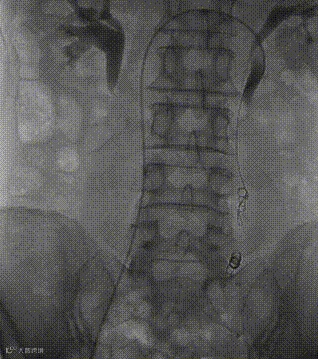

行高压造影显示:下腔静脉通畅,未见血栓、畸形;

行左侧肾静脉造影显示:左肾静脉通畅,可见迂曲粗大的左侧卵巢静脉;

导丝单弯导管配合超选入左侧卵巢静脉,手推造影剂示:左侧卵巢静脉迂曲扩张,中到重度返流。